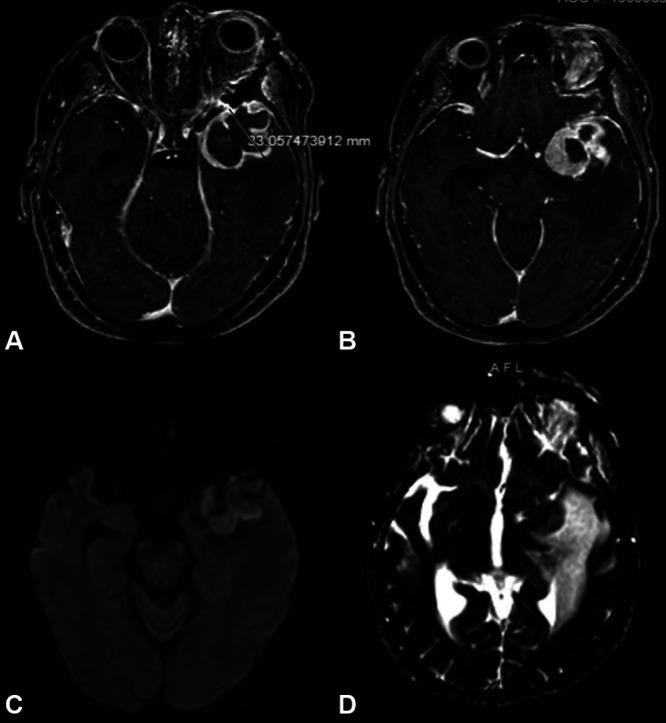

This is the second reported case of an intrameningioma abscess without a clear source of infection, occurring in a 70-year-old female with a history of transsphenoidal craniopharyngioma resection and radiation many years prior. She presented with severe fatigue and altered mental status initially ascribed to adrenal insufficiency, and magnetic resonance imaging showed a new heterogeneously enhancing left temporal mass with surrounding edema. After urgent tumor resection, pathology demonstrated a World Health Organization grade II meningioma (radiation induced). After a course of steroids and intravenous nafcillin, the patient recovered without neurological deficits.

这是第二例报道的无明确感染源的脑膜瘤内脓肿病例,发生在一名70岁女性身上,该女性多年前有经蝶窦颅咽管瘤切除术和放疗史。她最初表现为严重疲劳和精神状态改变,最初归因于肾上腺功能不全,磁共振成像显示左侧颞叶有一个新的不均匀强化肿块并伴有周围水肿。紧急肿瘤切除术后,病理显示为世界卫生组织II级脑膜瘤(放疗诱发)。经过一个疗程的类固醇和静脉注射萘夫西林治疗后,患者康复,无神经功能缺损。